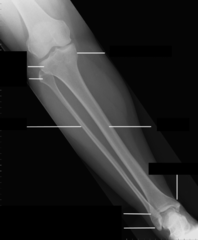

AP Tibia Fibula Comp Anatomy

Shaft of tibia

Tibial plateau

Medial condyle of tibia

Lateral malleolus

Lateral Condyle

Lateral condyle of tibia

Tibia

Fibula

Tibia tuberosity

apex of fibula

Intercondyle eminence

Anterior crest or tibial spine

Distal Tibiofibular joint

Head of fibula

Proximal Tibiofibular joint

Shaft of fibula

Medial Malleolus